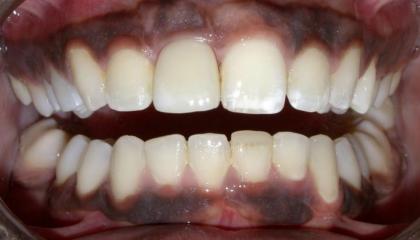

Before

After